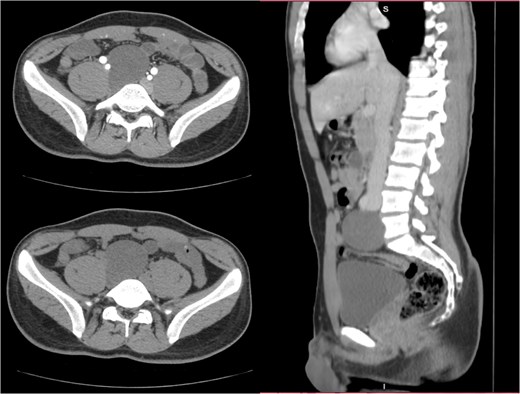

Given the clinical suspicion of acute appendicitis, a contrast-enhanced computed tomography (CT) scan of the abdomen and pelvis was performed (Fig. 1). The imaging confirmed acute appendicitis, demonstrating a fluid-filled and dilated appendix measuring up to 1 cm with periappendiceal fat stranding and free fluid. Additionally, an incidental finding of a well-defined, thin-walled, unilocular cystic lesion in the retroperitoneum, located inferior to the aortic bifurcation and anterior to the L5 vertebral body, was observed. The lesion measured ~6 × 6 × 6.5 cm and showed mild enhancement, raising the differential of a mesenteric cyst or neurogenic tumor.

The images provided show axial and sagittal CT views of a well-defined retroperitoneal mass located anterior to the L5 vertebra. The lesion appears encapsulated, homogenous, and slightly hypodense compared to surrounding structures.

Imaging techniques commonly used to detect retroperitoneal schwannomas include abdominal ultrasound, CT scans, and magnetic resonance imaging (MRI) [2]. Ultrasound typically reveals a homogenous, well-defined, and poorly vascularized lesion, although some studies have described central cystic areas with necrotic heterogeneity. CT scans often show a cystic mass with central necrosis, characteristic of schwannomas [5, 6]. In this case, the patient underwent a CT scan, which revealed findings consistent with acute appendicitis, including a fluid-filled and dilated appendix measuring up to 1 cm with surrounding periappendiceal fat stranding and minimal free fluid. Additionally, the CT scan incidentally identified a thin-walled, slightly enhancing unilocular cystic lesion in the retroperitoneum, located inferior to the aortic bifurcation and anterior to the L5 vertebral body. The lesion measured ~6 × 6 × 6.5 cm and displayed features suggestive of a benign retroperitoneal tumor, such as a well-defined and encapsulated appearance. These imaging findings, combined with surgical excision and histopathological analysis, confirmed the diagnosis of an ancient schwannoma. While procedures such as biopsy or CT-guided fine-needle aspiration biopsy can help confirm the diagnosis, they are generally avoided preoperatively due to the risk of complications like bleeding, infection, or tumor seeding [2].